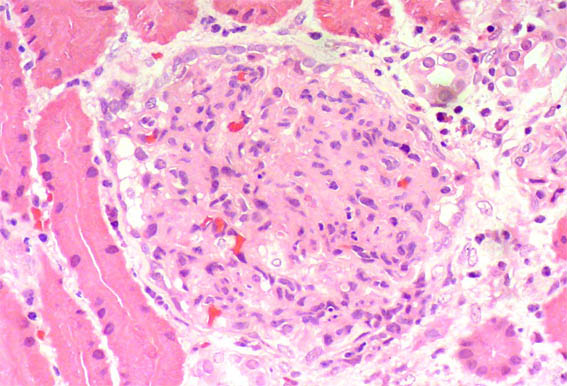

Figure 2. H&E, X400.